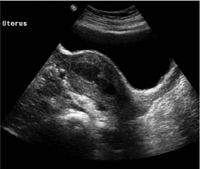

Stenosis Of Uterine Cervix